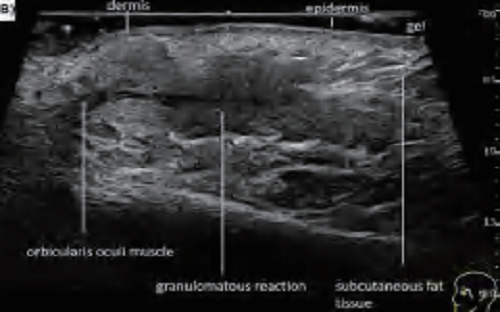

PAU2C aesthetic skin ultrasound device is portable and easy to use for aesthetic medicine. Handheld design allows aesthetic physicians to perform ultrasound whenever patients are in need. Aesthetic medicine ultrasound device works for medical beauty, clinic, hospitals, beauty salon. Our medical beauty ultrasound device that connects with WIFI without restrictions of wiring. Support windows, android, and IOS. Supported ultrasound exam presets for cosmetic medical services include fat factor, HA, PCL, CaHA, PLLA and PDLLA.

PAU2C is a game-changing ultrasound device for aesthetic and medical professionals, combining intuitive usability with advanced features to meet modern clinical and beauty workflow demands. Whether used to evaluate fat distribution, track filler efficacy, or assess tissue response, PAU2C delivers the precision, speed, and dependability professionals need for exceptional patient outcomes.